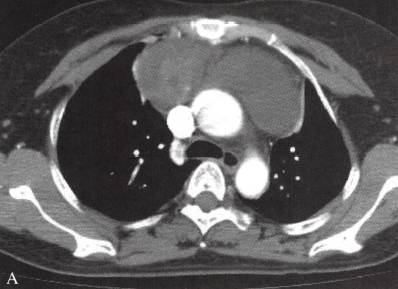

图2多房胸腺囊肿

女性,56岁,胸痛2周。A, B. CT示前纵隔肿物,大部分为囊性,壁厚,有分隔;右侧部分为实性,不均匀环形强化。术后病理为胸腺囊肿,囊壁内见炎细胞浸润、胆固醇结晶,伴出血、退变及坏死